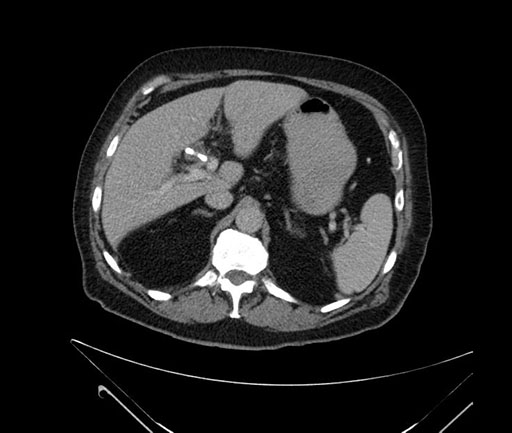

Coronal - stented